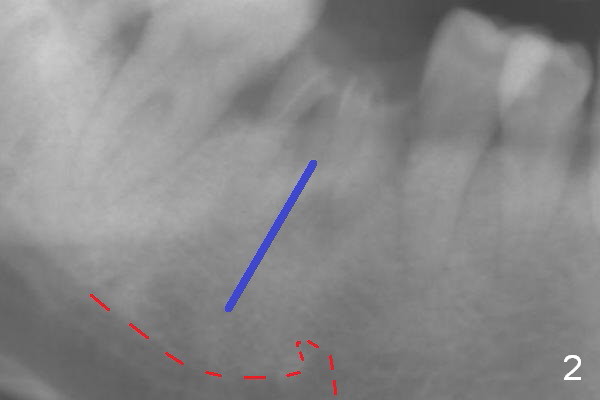

A 37-year-old woman is afraid of dentistry and procrastinates implant restoration at #30 (Fig.1).  The opposing tooth is supraerupted (arrow) and warrants occlusal adjustment for #30 immediate provisional.  Since there are 3 roots associated with #30 (*), the septum should be tripod, where osteotomy will be established after Clindamycin socket application.  Primary stability of the immediate implant is further enhanced by the bone height.  It is expected to gain ~ 6 mm in the native bone (Fig.2 blue line).  As long as the osteotomy is slightly longer than the 2nd molar, there is minimal chance to involve the superior border of the Inferior Alveolar Canal (red dashed line).  Magic Split and Expanders are to be used in combination with drills if necessary.  Photograph the septum before and after osteotomy.

The 2nd method of osteotomy is to use 3.8 or 4.3 mm drill (after marking drill) in the middle of the septum at the depth determined by preop PA after removal of the coronal portion of the residual roots with high speed handpiece.  Keep the drill in place for intraop PA.  Remove the roots.  A 4.5x13 mm implant will be placed.  Either way, prepare PRF.